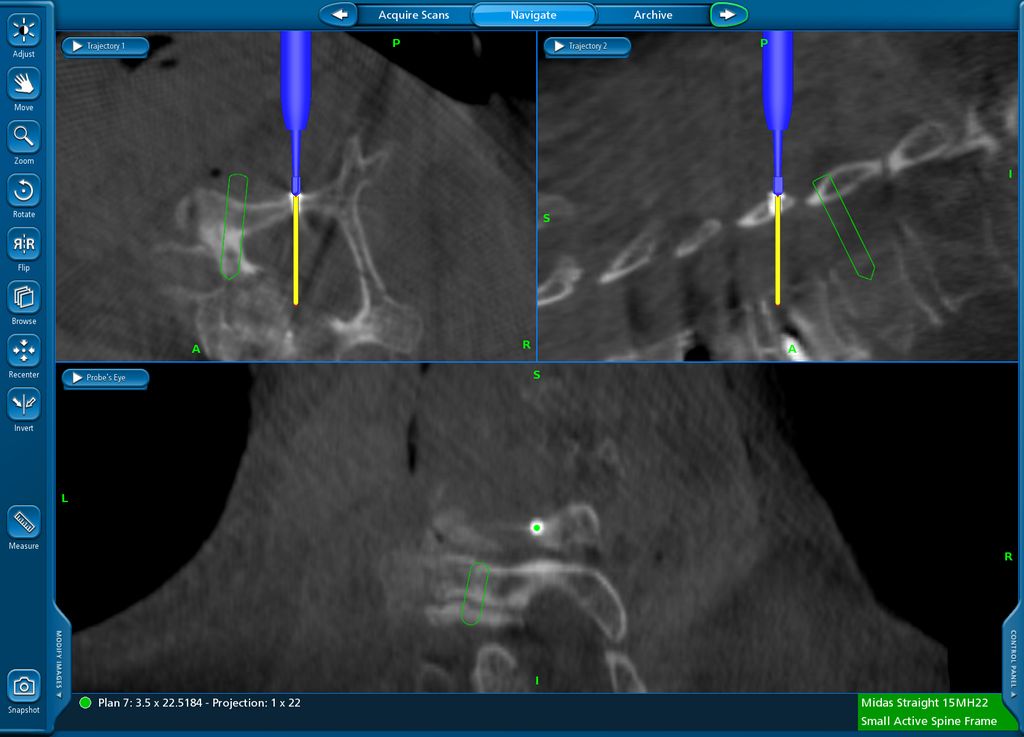

Fallbeispiel 3

Navigierte Implantation eines „interbody device“ über lateralen Zugang (XLIF; „Xtreme lateral interbody fusion“). Bei der 79-jährigen Patienten kam es nach Fusion L4/5 vor mehr als 10 Jahren zu einer symptomatischen Anschlusssegmentdegeneration L3/4 mit Schmerzen im Dermatom L4 beidseits sowie zu Lumbago. Es erfolgte navigiert die Implantation eines Zugangs in Rechtsseitenlage. Intraoperativ wurde die Referenz am Beckenkamm platziert (Abb. 12) und mit intraoperativem CT (O-Arm) ein 3D-Datensatz gewonnen. Anhand dessen können Instrumente wie Küretten oder Raspatorium (Abb. 13) wie auch die Implantation des Cages selbst (Abb. 14) navigiert werden. Das postoperative Röntgen zeigt einen regelrechten Implantatsitz (Abb. 15).